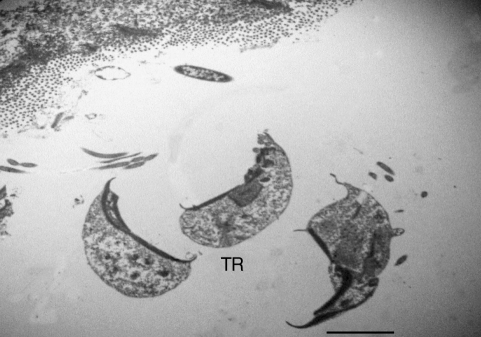

Fig. 2A TEM photo of Cochlosoma trophozoites (TR) within the intestinal lumen of the turkey poult. Bar = 4 µm.

Fig. 1). Some of which seem to be firmly attached to the gut epithelial lining. In TEM studies on parasagittal sections, the trophozoites of the organism was a uninuclear, conical, or pyriform-shaped flagellated cell with a prominent ventral sucker-like disc (

Figs. 2-

4). There were sharp points at the posterior and anterior ends of the ventral sucker and 6 flagella emerging from an opening space of ventrodorsal surface of the parasite (

Figs. 3,

4). In cross sections, the sucker seemed to be concave and had an electron dense free sharp edge. The morphological characteristics of the organism are in agreement to those described for